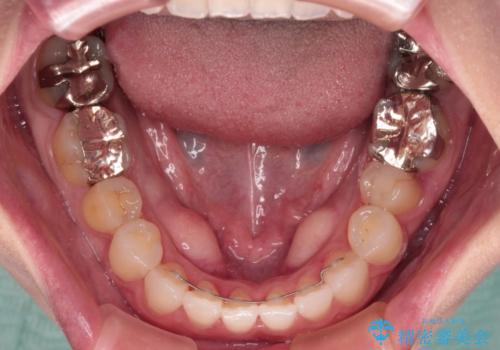

前歯のデコボコをすっきりと インビザライン矯正

- 前歯のデコボコを治したいとのことで来院された患者様です。

下顎が前方位にある方であったため、下顎の歯列全体の後方移動とIPR(歯と歯の間を削る)によってデコボコが解消するように設計し、インビザラインにより治療を行うこととしました。